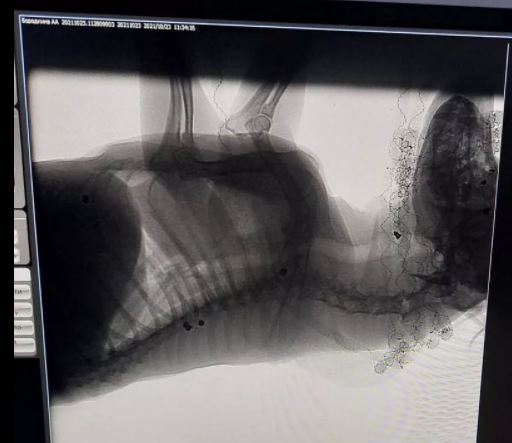

Неделю назад небезразличные жители, неподалеку от зооклуба «Неон», обнаружили раненую собаку. После осмотра ветеринаром и рентгеном в теле животного было обнаружено 7 пуль. Одна из них застряла в шее и мешала животному принимать пищу.

Достать остальные пули, по сообщению волонтеров, бердянские врачи не берутся. Животное нуждается в серьезной операции. Активисты объявили сбор средств на спасение жизни собаки.

Характер ранений и пули позволяют заключить, что пса расстреливали из пневматического оружия. Подобные случаи в Бердянске не редкость. Живодеры безнаказанно издеваются над животными ради извращенного удовольствия.